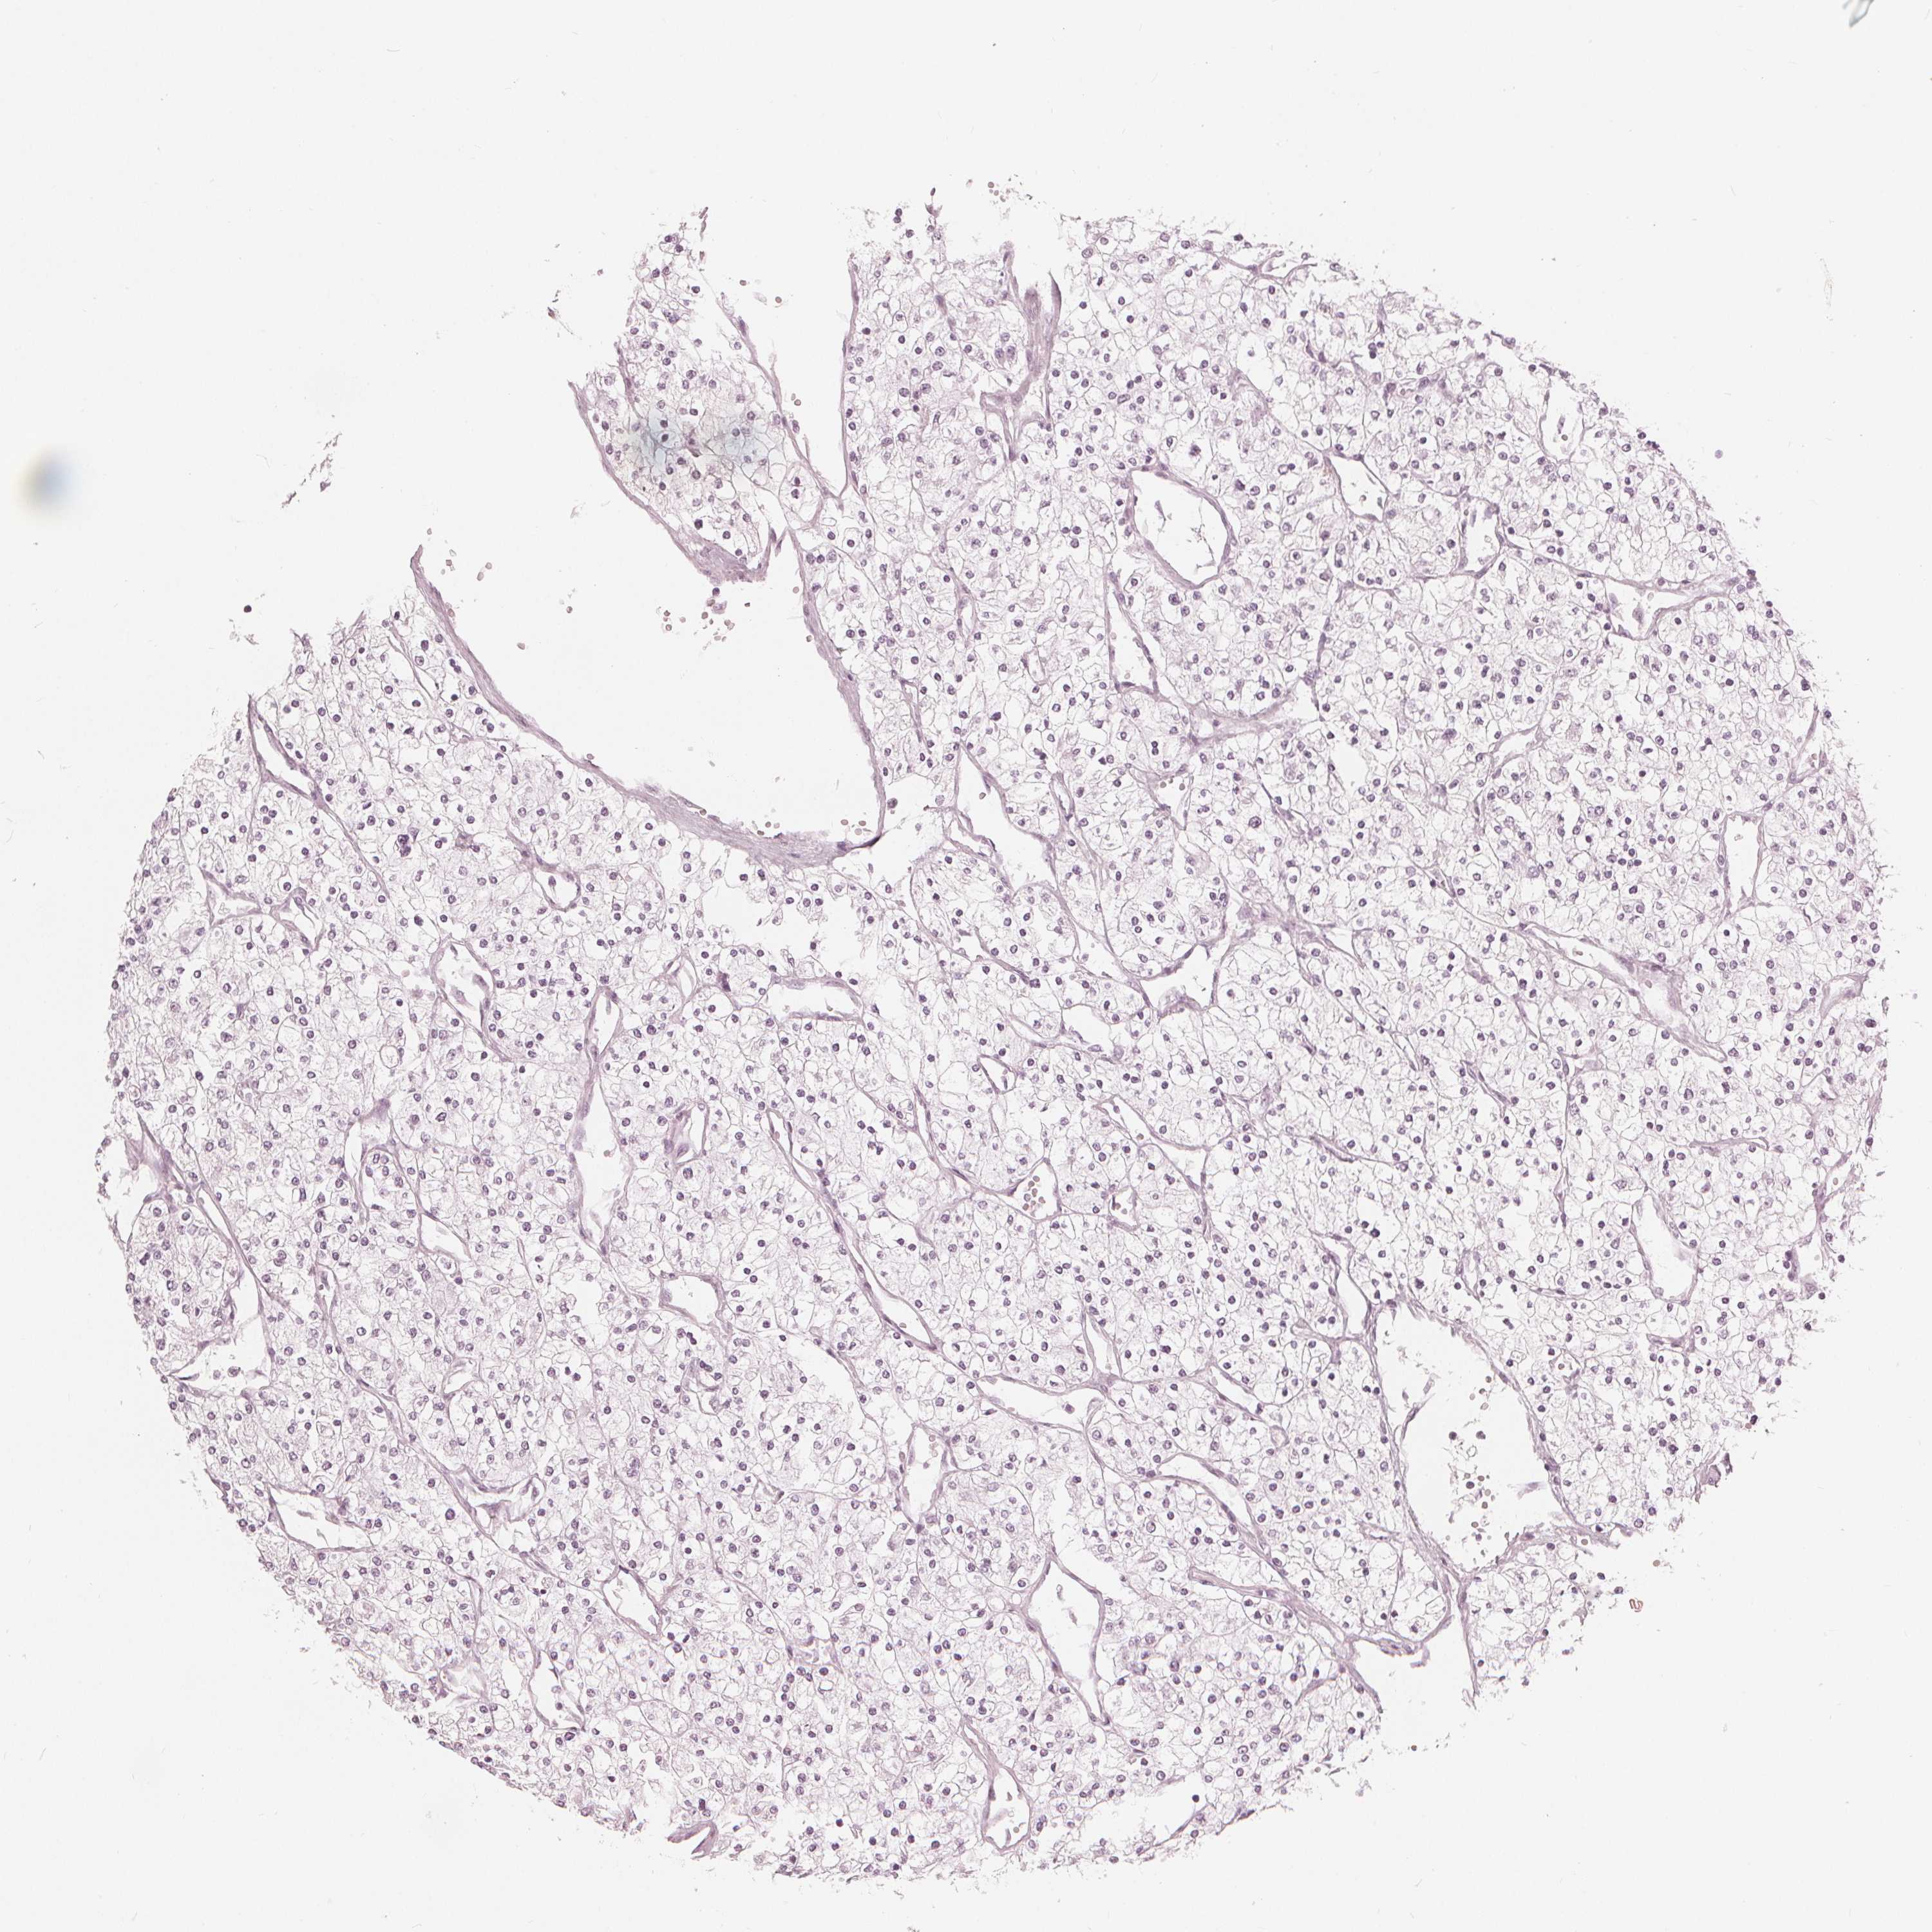

KIDNEY RENAL CLEAR CELL CARCINOMA (VALIDATION) - Interactive survival scatter ploti

The Survival Scatter plot shows the clinical status (i.e. dead or alive) for all individuals in the patient cohort, based on the same data that underlies the corresponding Kaplan-Meier plots. Patients that are alive at last time for follow-up are shown in blue and patients who have died during the study are shown in red.

The x-axis shows the expression levels (FPKM) of the investigated gene in the tumor tissue at the time of diagnosis. The y-axis shows the follow-up time after diagnosis (years). Both axes are complimented with kernel density curves demonstrating the data density over the axes. The top density plot shows the expression levels (FPKM) distribution among dead (red) and alive patients (blue). The right density plot shows the data density of the survived years of dead patients with high and low expression levels respectively, stratified using the cutoff indicated by the vertical dashed line through the Survival Scatter plot. This cutoff is automatically defined based on the FPKM cutoff that minimizes the p-score. The cutoff can be changed by dragging the vertical line or by entering a cutoff value in the square labeled "Current cut-off".

Under the Survival Scatter plot the p-score landscape (black curve; left axis) is shown together with dead median separation (red curve; right axis). Dead median separation is the difference in median mRNA expression between patients who have died with high and low expression, respectively. It is calculated as follows: median FPKM expression of dead patients with high expression - median FPKM expression of dead patients with low expression. This is intended to aid the user in visually exploring custom cutoffs and the associated p-scores and dead median separation.

Individual patient data is displayed and can be filtered by clicking on one or more of the category buttons on the top of the page. Categories describing expression level and patient information include: high, low, alive, dead, female, male and tumor stages. The scale of the x-axis can be toggled between linear and log-scale by clicking on the "x log" button. Mouse-over function shows TCGA ID, patient information and mRNA expression (FPKM) for each patient.

& Survival analysisi

Kaplan-Meier plots summarize results from analysis of correlation between mRNA expression level and patient survival. Patients were divided based on level of expression into one of the two groups "low" (under cut off) or "high" (over cut off). X-axis shows time for survival (years) and y-axis shows the probability of survival, where 1.0 corresponds to 100 percent.

PAEP is validated prognostic, high expression is unfavorable in Kidney Renal Clear Cell Carcinoma (validation)

Best expression cut offi

Based on the FPKM value of each gene, patients were classified into two groups and association between prognosis (survival) and gene expression (FPKM) was examined. The best expression cut-off refers the FPKM value that yields maximal difference with regard to survival between the two groups at the lowest log-rank P-value. Best expression cut-off was selected based on survival analysis .

When clicking on this number, the vertical dashed line indicating cut-off, the interactive survival plot, and the Kaplan-Meier curve will be adjusted to show results based on the best expression cut-off.

: 0.84

Average pTPM 4.7

Number of samples 100